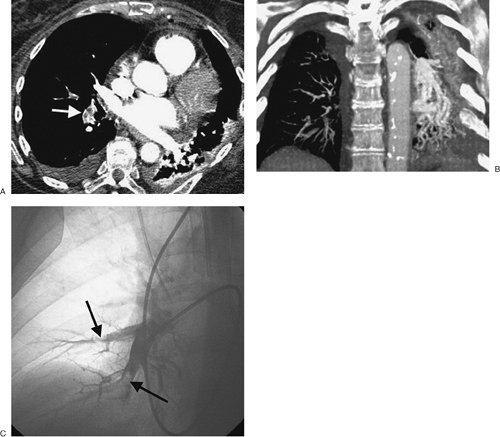

FIGURE 17-4. Acute PE. A: CTPA of a 77-year-old woman with a gastrointestinal bleed and DVT shows an intraluminal filling defect in a left lower lobe segmental pulmonary artery (arrow). B: CTPA at a more superior level shows intraluminal filling defects, surrounded by contrast material, in the right middle lobe and left lower lobe pulmonary arteries (arrows). C: CTPA at a level superior to (B) shows an intraluminal filling defect, surrounded by a thin rim of contrast material, in a right lower lobe segmental pulmonary artery (arrow).